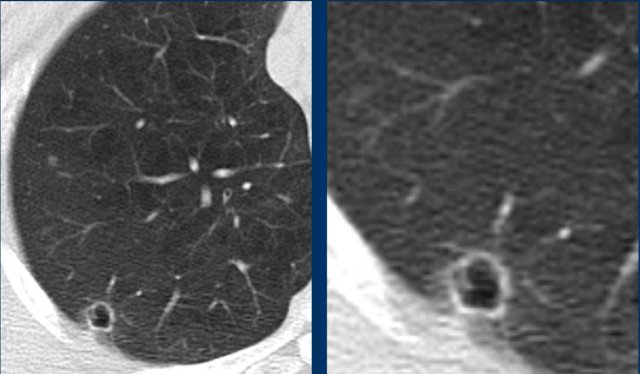

These images are of a 58 year old man with Covid infection since a week.

Bilateral ground-glass with multiple small cyst-like lesions.

This could be mistaken for a cystic lung disease or for infection with pneumatoceles.

But notice the subtle ‘central dot’ in some of the lesions (yellow arrows) and in the detail (black arrow).

This is consistent with centrilobular emphysema.

The emphysema is better visible due to the surrounding ground-glass.